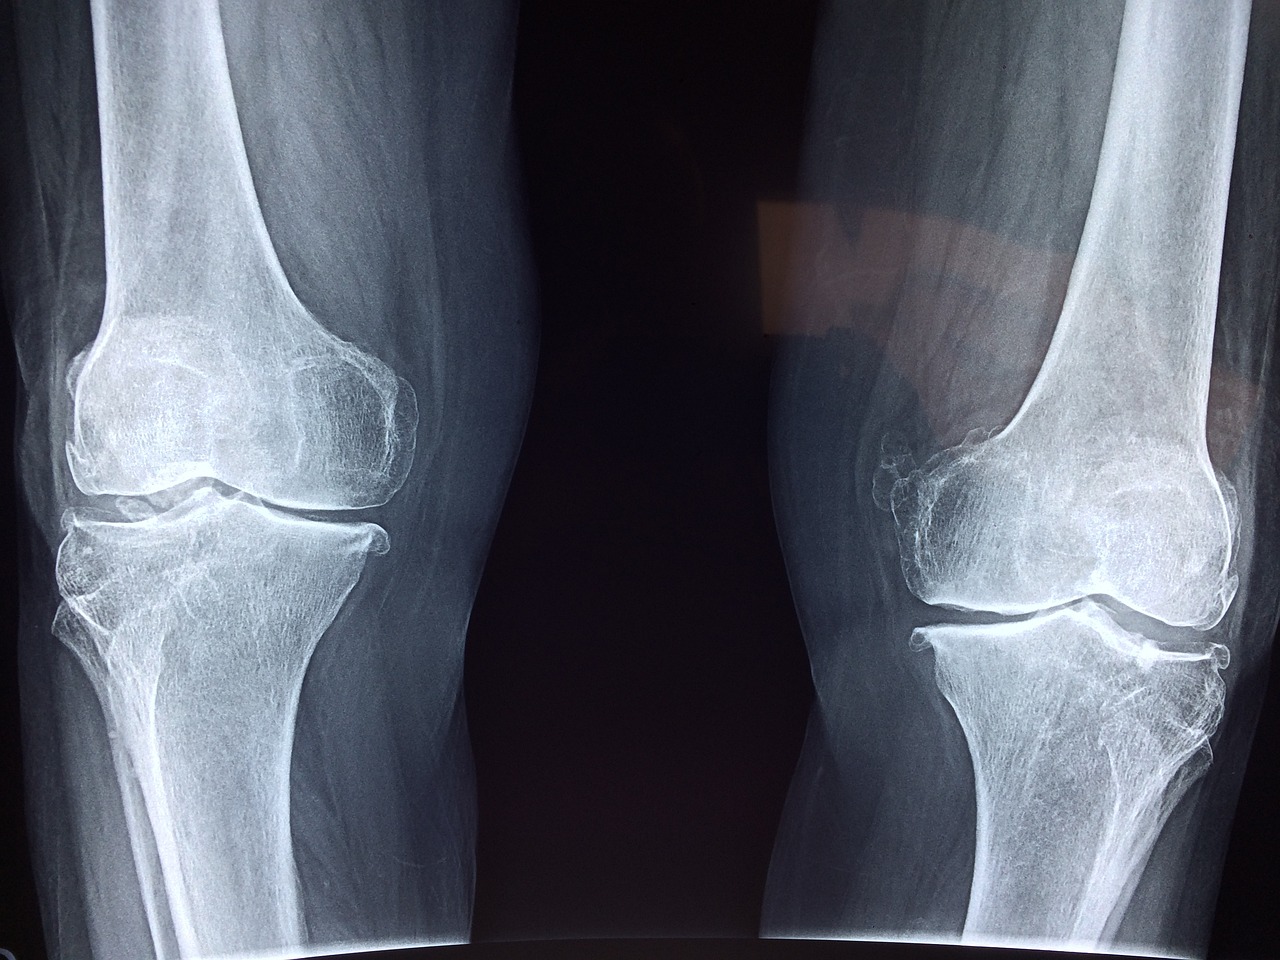

관절염은 그리스어로 관절을 의미하는 "arthro"와 염증을 의미하는 "itis"에서 파생된 용어입니다. 이는 움직임을 허용하는 뼈 사이의 결합 조직인 관절에 영향을 미치는 만성 장애입니다. 가장 흔한 형태는 골관절염으로, 관절 연골과 밑에 있는 뼈의 퇴화를 특징으로 하며 통증과 관절 운동의 제한을 초래합니다. 반면, 류마티스 관절염은 면역체계가 관절을 둘러싸는 막의 내벽인 윤활막을 공격하는 자가면역 질환입니다.

가장 흔한 형태인 골관절염은 종종 노화와 시간이 지남에 따라 관절에 누적되는 마모와 관련이 높습니다. 이는 비만, 관절 부상, 반복적인 스트레스와 같은 요인으로 인해 악화될 수 있습니다.